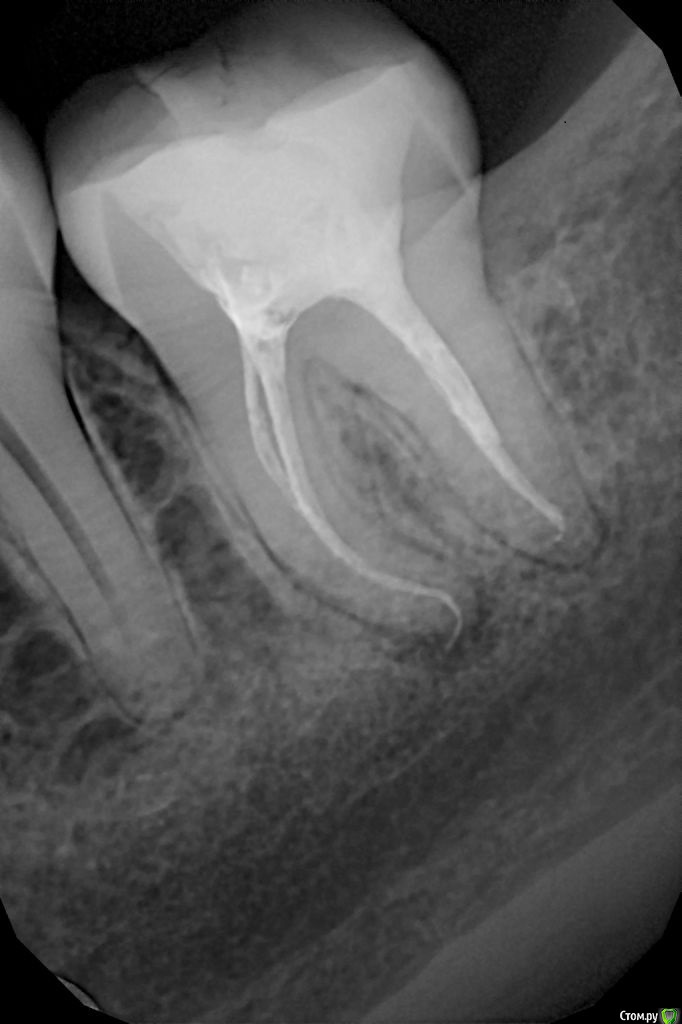

katrineigma Опубликовано 3 декабря, 2015 Поделиться Опубликовано 3 декабря, 2015 Добрый день!Полгода назад вылечила зуб. Уже 2 месяца он непрерывно ноет (есть на него не больно) Прикрепляю рентгены сразу после лечения и спустя 4 месяца (с воспалением). Врачи не берутся перелечивать - говорят зуб сложный и есть риск его вообще потерять. А в той клинике, где лечили зуб изначально, говорят, что все хорошо, в нем изначально было воспаление (разве было?) это так зуб реагирует на лекарство, это наоборот лечение идет, просто у вас такие индивидуальные особенности организма (прошло уже полгода с момента лечения! И как может зуб реагировать на лекарство воспалением?) Делали сегодня ЭОД этого зуба, показатель был 74 мкА, но ничего внятного по этому поводу не сказали. Подскажите, пожалуйста, для депульпированного зуба что значит этот показатель? Меня врачи очень сильно водят за нос, судя по всему.Заранее спасибо. Ссылка на комментарий

katrineigma Опубликовано 5 декабря, 2015 Автор Поделиться Опубликовано 5 декабря, 2015 А какой у Вас характер боли?Может причина в другом зубе?Спасибо всем за комментарии!Характер боли - постоянная ноющая, когда-то сильнее, когда-то слабее, с самого утра не болит, через полчаса-час уже ноет, и так каждый день. Жевать на зуб не больно. Соседние зубы леченые тоже недавно и на них показатель ЭОД - 4. Здесь же очевидное воспаление на рентгене...думаете, причина боли может быть не в нем? Ссылка на комментарий

DmitrySH Опубликовано 5 декабря, 2015 Поделиться Опубликовано 5 декабря, 2015 Сложно дать ответ на основании только снимка. Но ревизию каналов лучше сделать. 2 Ссылка на комментарий